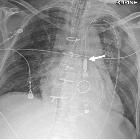

CT and chest

radiography in evaluation of mechanical circulatory support devices for acute heart failure. Protek Duo for right ventricle support. AP Chest radiograph with CLAHE filter after Protek Duo placement (a) demonstrating right basilar and mid-lung opacities. The outlet cannula portion should be in right ventricle and the inner portion within the pulmonary artery. In this case, the outlet cannula tip is within the right pulmonary artery. This can cause asymmetric perfusion and edema. Axial CT (b) in mediastinal window demonstrates asymmetric pulmonary opacities, right pleural effusion and a hemothorax (white arrow). (CLAHE—contrast limited adaptive histogram equalization)